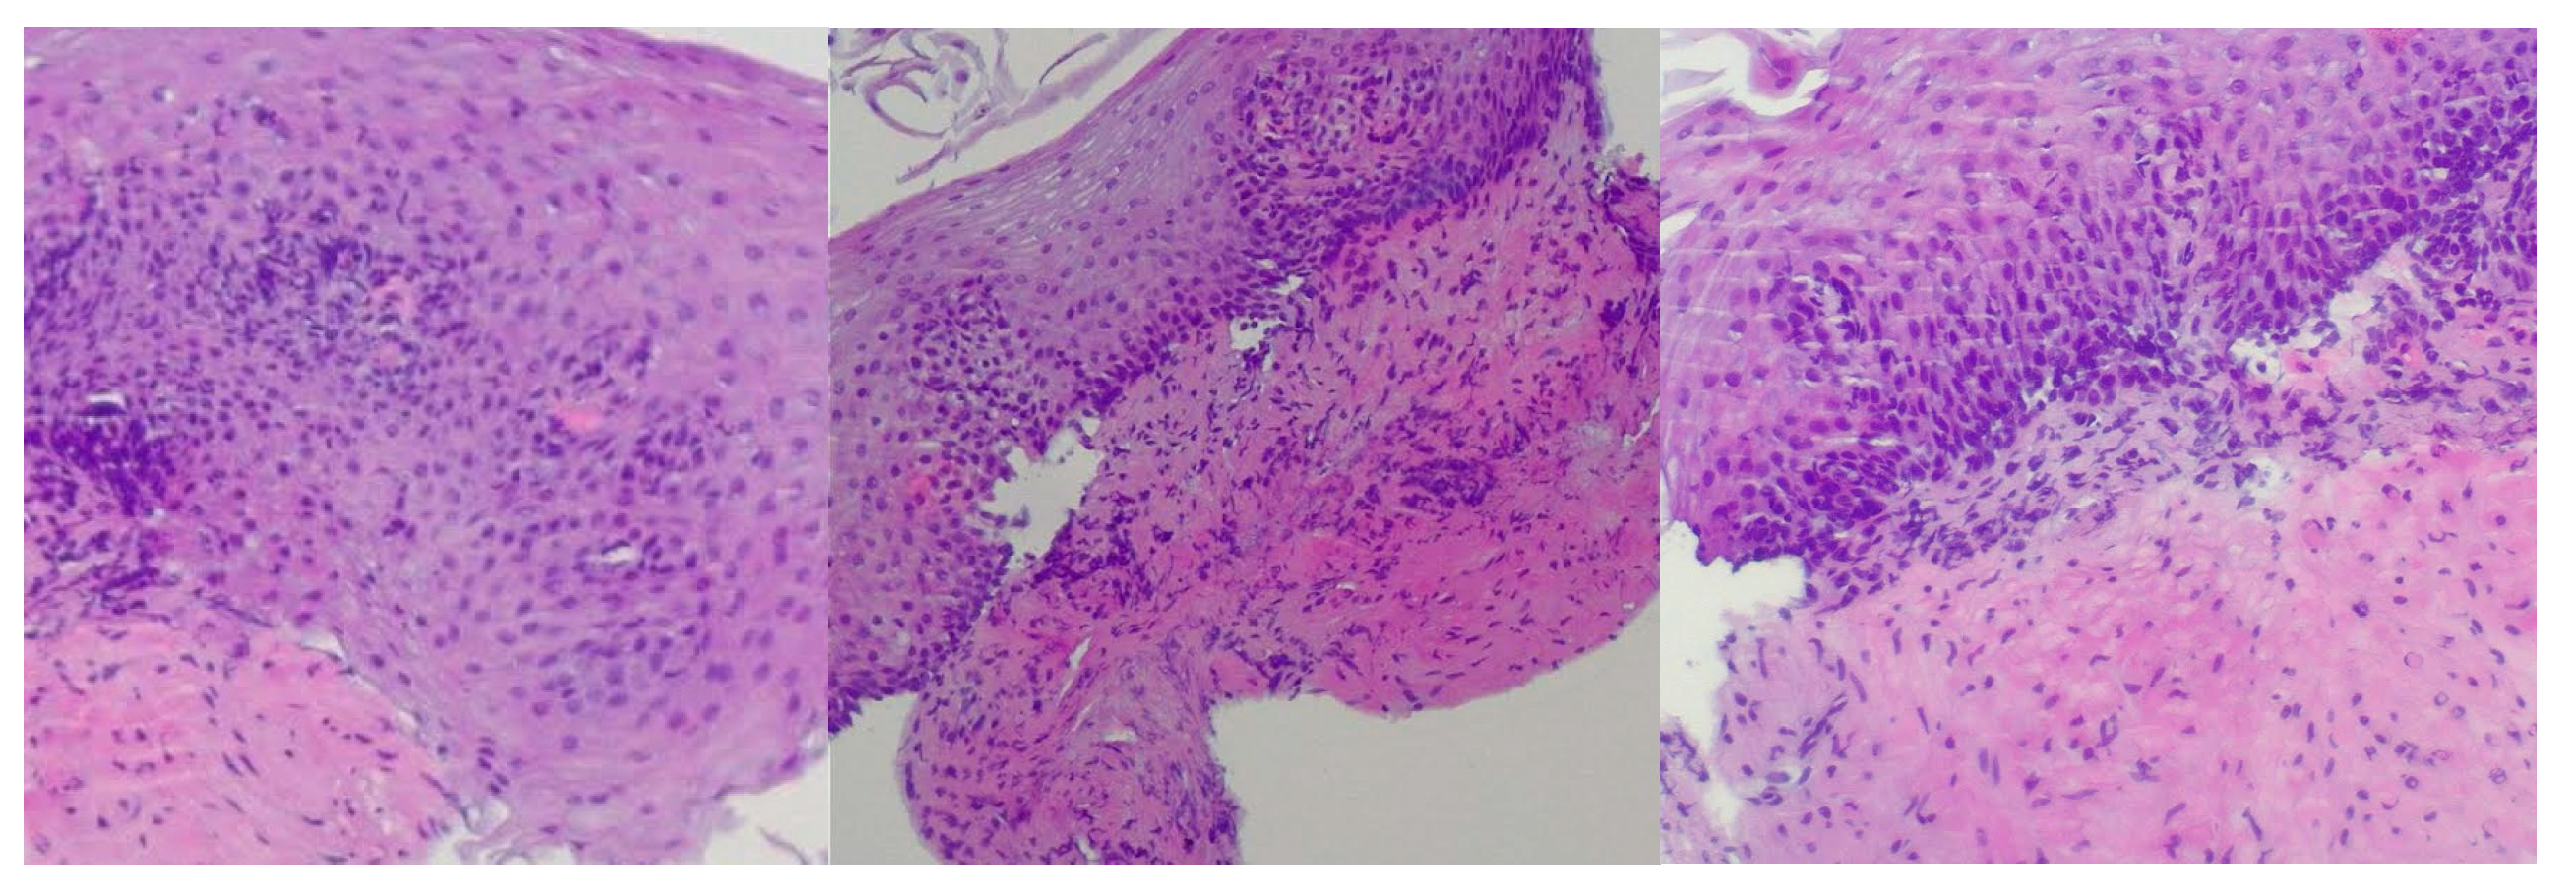

Reflux esophagitis was confirmed by biopsy findings showing stratified squamous epithelium, basal layer hyperplasia, chronic inflammatory infiltrate in the lamina propria, acanthosis, papillomatosis, and focal neutrophilic granulocytic infiltration within the papillary axes (Figure 1).

Figure 1. Microscopic signs of reflux esophagitis. Biopsy findings showing stratified squamous epithelium, basal layer hyperplasia, chronic inflammatory infiltrate in the lamina propria, acanthosis, papillomatosis, and focal neutrophilic granulocytic infiltration within the papillary axes. The images, from left to right, are magnified at ×400, ×200 and ×400.